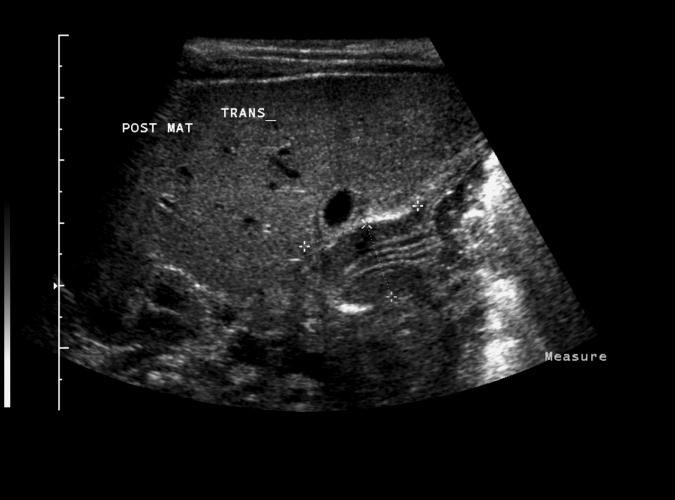

Pylorusstenos